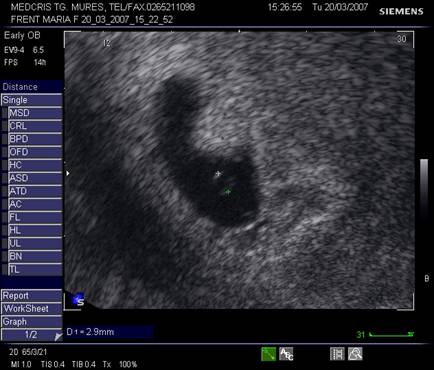

Oul clar este definit ca o sarcina anembrionata si fara sac Yolk (cca 1/3 din avorturile spontane) [10].

Incidenta anomaliilor cromozomiale este mai mare decat la avorturile cu embrion prezent, in special a trisomiilor. Ecografia transvaginala va indica un sac gestational gol, a carui marime este corespunzatoare relativ la durata amenoreei, eventual cu usor contur neregulat.

Pentru a nu face o eroare de diagnostic in prezenta unui sac gestational prea mic , posibil al unei sarcini incipiente, o reevaluare la o saptamana va fi necesara.

Fig. nr. 82 Ou clar la ecografia transvaginala